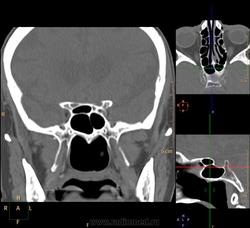

Одна пазуха: